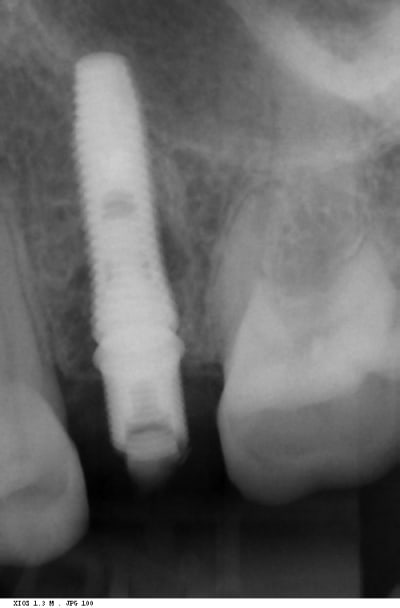

Vissage d’un dentium superline SLA en 4x14mm bloqué à 30N.cm, je monte à 55.

L’implant est enfoui en D, il manque 5 mm en P, 1 en M, et 8 en V.

Suture et radio.